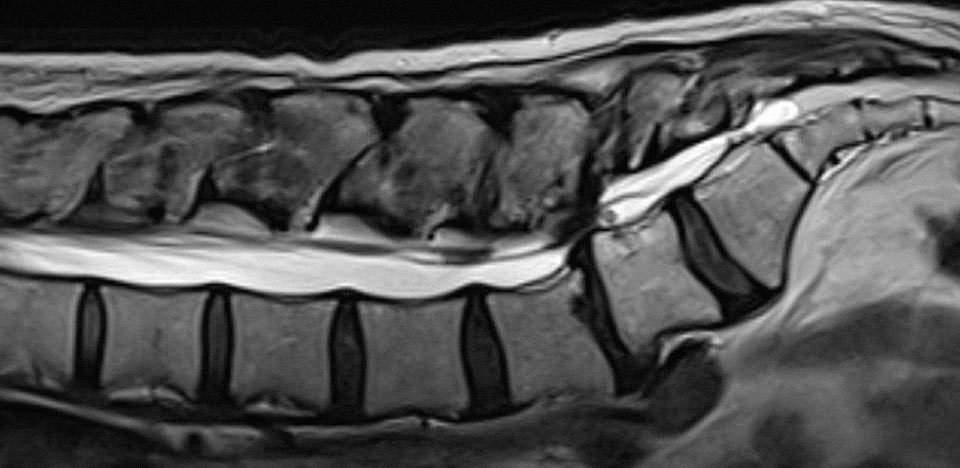

• 디스크는 척추 사이의 충격 완충 역할을 하는 구조가 파열되거나 탈출해 신경을 압박하는 질환입니다.

• 통증, 보행 장애, 마비 등이 빠르게 진행할 수 있어 조기 진단과 적절한 치료가 매우 중요합니다.

• 심한 압박이 확인되면 수술로 신경을 감압해 기능 회복을 돕고, 재발 가능성을 줄일 수 있습니다.